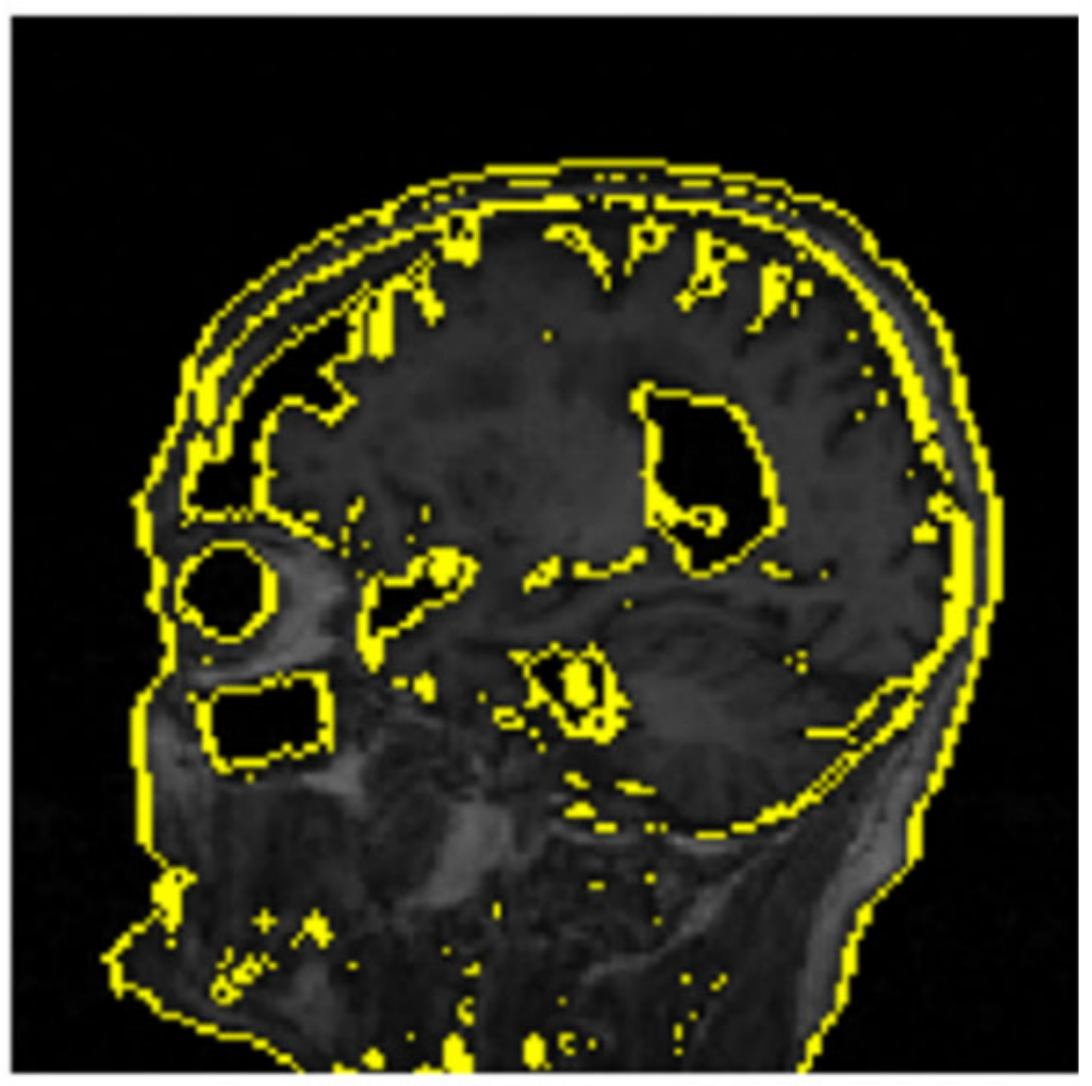

The confusion matrix in Figure 4 displays the network’s predictive performance on the three classes: NC (normal cognition), MCI (mild cognitive impairment), and AD (Alzheimer’s disease). Figure 3 is a visualization of the deep learning model’s performance where the highest training accuracy of 85% is displayed, calculated through Equation (5). The training process was stopped as the model had 0 out of 23,587,712 trainable parameters. Figure 4 visually represents the label predictions using the confusion matrix. One example from the test set produced a positive prediction for mild cognitive impairment (MCI), as shown in Figure 5. This image served as the input for our XAI experiments.

Given that the LIME methodology includes perturbing the instance x , sampling perturbed instances z from the neighborhood, obtaining predictions from the black box model f , and fitting an interpretable model g to locally approximate f s behavior, the interpretable representation X is utilized to emphasize significant features or regions represented by superpixels. The deactivation of these pixels returns a greyed-out representation of excluded features in the model’s prediction (Figure 6). Conversely, the activation of superpixels returns a mapping of feature regions that were relevant to the model’s prediction (Figure 7).

Figure 6. Perturbed instances from the predicted image in Figure 5 showing deactivated pixels.